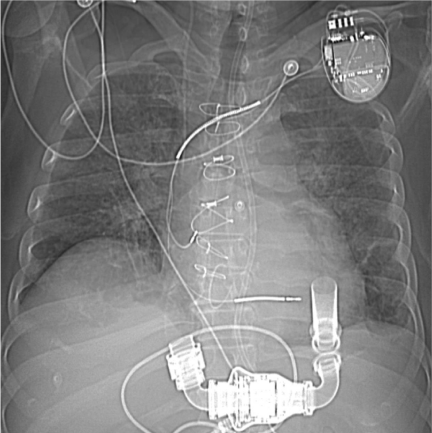

Vital signs on presentation at the outside hospital were: Temperature 38.1 F, Heart Rate of 90-101 beats/minute, Respiratory Rate 20-40 breaths/ minute, mean arterial pressure of 70 mmHg and oxygen saturation of 94% on VentiMask 40%. On examination at our hospital he was found to be tachypneic at 33 breaths/minute requiring Bi-level positive airway pressure (BiPAP), heart rate-106 beats/minute, mean arterial pressure-64 mmHg and oxygen saturation of 90% on VentiMask 40%. He appeared confused and lethargic. Neck exam was positive for jugular venous distension. He had decreased breath sounds bilaterally and the LVAD hum was heard on cardiac exam. On neurologic exam, he did not follow any commands, was aphasic with a right facial droop and had right hemiplegia. On checking with the outside hospital, due to his acute distress and lethargy, a neurologic exam was not performed. Laboratory tests on admission were consistent with hemolysis and acute renal failure (Table 2). LDH was elevated at 3012 (IU/L) up from<500 a week ago. Chest radiography was consistent with pulmonary edema (Figure 1). CT Head revealed a left non-hemorrhagic MCA infarct with mild mass effect and mild midline shift from left to right (Figure 2). Urine in his Foley bag was orange- red in color. A stat echocardiogram (Figure 3) obtained revealed a dilated left and right ventricle and an aortic valve opening every beat that was opening every other beat on his last clinic visit, 3 weeks ago. This further confirmed the working diagnosis of an acute LVAD thrombus complicated by an embolic event leading to the acute ischemic infarct. An emergent Neurology consultation was obtained and after reviewing his physical exam and CT-brain with the Neurology team, the diagnosis of acute ischemic stroke with significant right hemiplegia was confirmed. Since he was outside the recommended treatment window for thrombolytic administration for his acute stroke (9hours against the recommended, the Neurology team recommended against the use of systemic thrombolysis due to the increased risk for bleeding vs. reducing infarct size.

Figure 2 CT- Head at Presentation. Large left non- hemorrhagic middle cerebral artery infarct with mild mass effect.